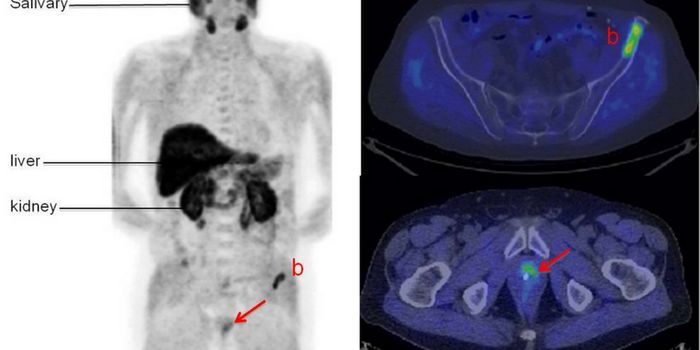

JUN 29, 2017CancerMost cancers kill by invading distant parts of the body where treatment is more difficult to reach. But cancer’s a ...